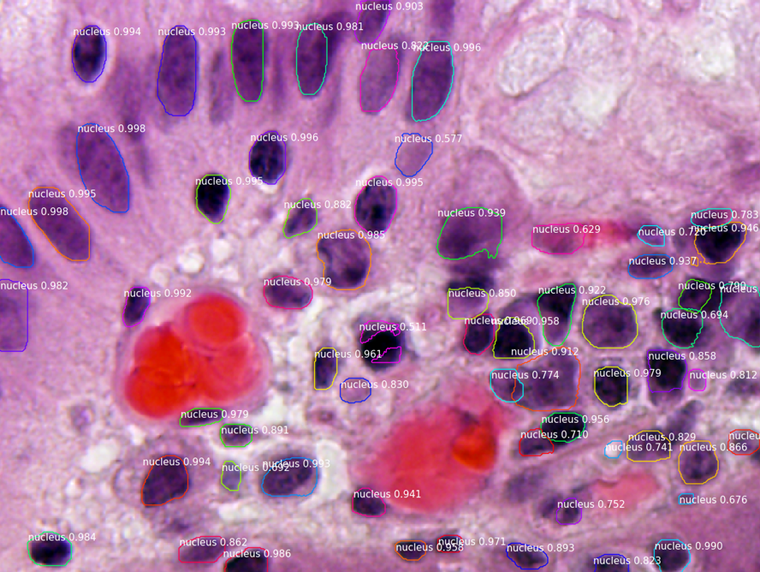

Segmenting Nuclei in Microscopy Images. Built for the 2018 Data Science Bowl

Code is in the samples/nucleus directory.